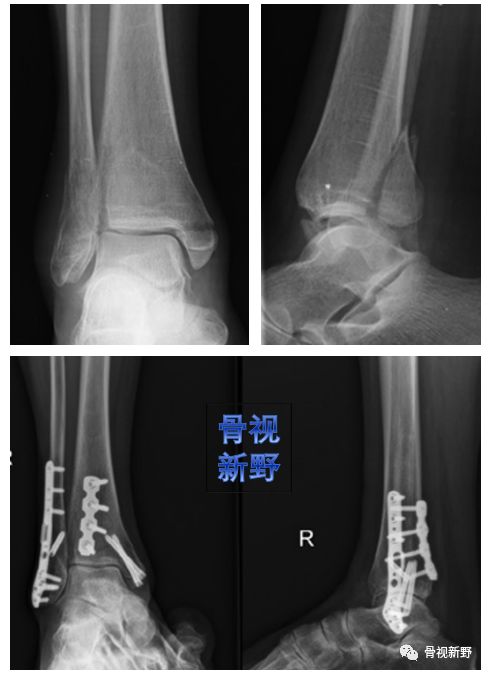

内踝垂直型骨折的buttress固定

内踝骨折根据骨折线走形方向可分为:横形、斜形、粉碎、垂直骨折,其中斜形、垂直形,特别是垂直型骨折的剪力较大,常规克氏针、空心钉、张力带等固定措施不能很好中和剪切力,应用buttress钢板的防滑原理可减少不愈合及畸形愈的并发症。

内踝斜形骨折—腓骨远端锁定钢板防滑固定(J Foot Ankle Surg. 2015 ;54(6):1202-5.)

腓骨远端锁定板防滑+克氏针防旋固定

锁定重建板单皮质固定防滑+空心钉加压固定

后踝/后Pilon骨折的buttress固定

后踝骨折和后Pilon骨折的界限一直不是很清楚。一般认为旋转性损伤机制、骨折块小、没有压缩的胫骨远端后方骨折属于后踝骨折,而跖屈损伤机制、骨块大、有压缩者往往属于后Pilon骨折。不稳定、较大骨块的后踝骨折及后Pilon骨折用空心钉固定有可能不能很好地中和向上的剪力,可选择butress钢板作防滑固定,以对抗垂直剪力。

锁定重建板作buttress钢板

锁定“T”型钢板作buttress钢板

3.5mm干骺端锁定钢板作buttress钢板